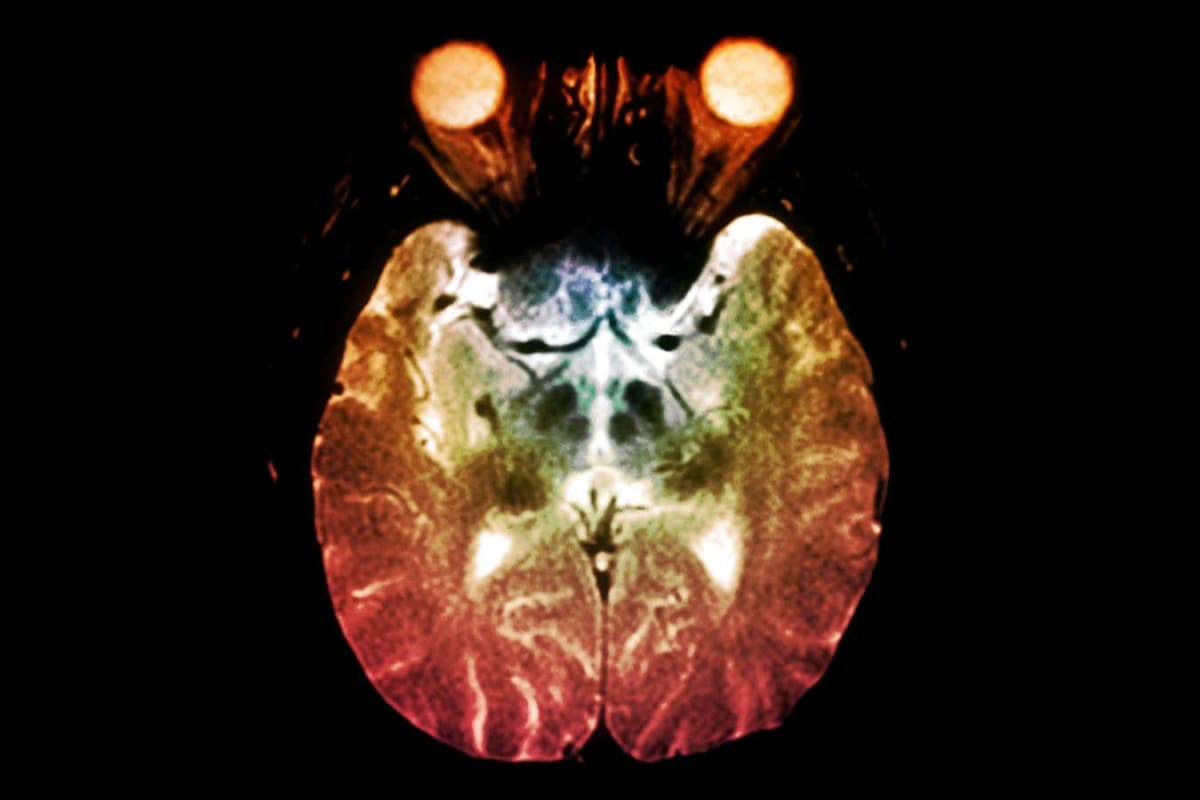

Parkinson's disease affects over 10 million people globally and happens when nerve cells in parts of the brain that control movement start to die. Scientists believe this occurs because misfolded proteins called alpha-synuclein build up into clumps, jamming the brain's natural waste disposal system.

The drug works by boosting slow brainwaves during deep sleep, which revs up the brain's glymphatic system. Think of it like turning up the power on your brain's natural cleaning crew. This enhanced cleanup reduced toxic protein clumps in the movement control areas of the brain by 40 percent more than the placebo.